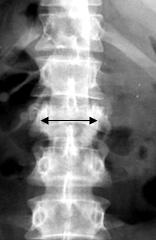

Признаком взрывных переломов, выявляемых при обзорной рентгенографии, является увеличение интерпедикулярного расстояния на прямой рентгенограмме (рис. 2А), увеличение переднезаднего размера тела позвонка - на боковой (рис. 2Б) и локальная кифотическая деформация в зоне перелома.

|

| А |

Б |

| Рис. 2. Рентгенологические признаки взрывного перелома тела позвонка |